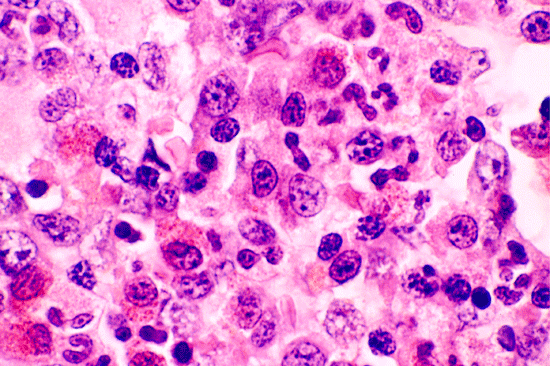

A bone marrow biopsy was performed. The followings are representative photos taken from the bone marrow biopsy:

Com401-1-B1.gif (137270 bytes) Com401-1-B2.gif (127871 bytes) Com401-1-B3.gif (174580 bytes) Com401-1-B4.gif (156845 bytes) Com401-1-B5.gif (138860 bytes)